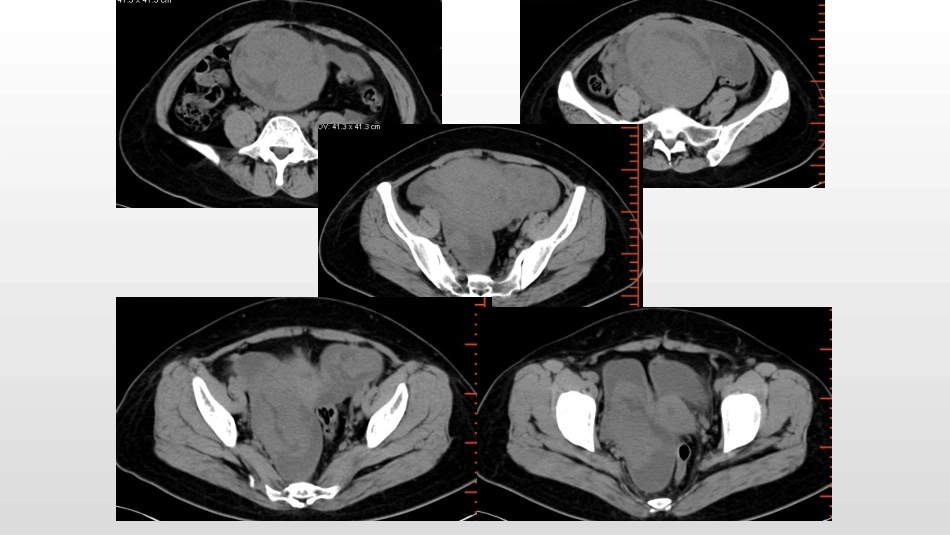

子宫肌瘤影像在此输入您的封面副标题病例5•女,33岁,已婚•患者平素月经规则,3-4天/30天,近两月月经不规则,量少,一周前感腹部坠胀,2016.9.5日外院门诊行腹部彩超示:脐下腹腔内可见一范围约175*83*147mm低回声团,其下段形态欠规则并与子宫分界不清。盆腹腔实质占位性改变,盆腔积液,未予特殊处理。今为求系统诊治,遂来我院门诊就诊,门诊医师遂以“盆腔肿物”将其收住院。•入院时诉有下腹坠胀,伴有腰痛,睡眠较差,饮食可,大小便正常。•妇检:外阴已婚型,阴毛分布正常,阴道光滑通畅,宫颈光滑,盆腔可触及一小足球大小包块,质偏硬,活动差,无压痛,双侧附件触及不满意。•辅助检查:2016.9.5日松滋中医院门诊行腹部彩超示:脐下腹腔内可见一范围约175*83*147mm低回声团,其下段形态欠规则并与子宫分界不清。盆腹腔实质占位性改变,盆腔积液。•6.2006年于松滋斯家场卫生院行剖宫产。既往否认心、肝、肾等慢性病史,否认乙肝、结核等传染病史,否认其他手术、外伤及输血史。手术及病理•手术记录:2016年09月19日在全麻下行经腹行子宫肌瘤剔除术+双侧阔韧带肌瘤剔除术,术中可见肌瘤分别约为190*150*70cm左右浆膜下肌瘤样组织,其根部长约5cm,双侧阔韧带处分别有一10*9cm、12*10cm肌瘤样组织,双侧输卵管及卵巢未见异常。•术后病检:(腹腔、左侧阔韧带,右侧阔韧带)梭形细胞肿瘤,考虑为平滑肌瘤。子宫平滑肌瘤(uterineleiomyoma)•子宫平滑肌瘤为最常见的子宫肿瘤,在育龄妇女中发生率在20%~25%•肿瘤常多发,也可单发•发病与雌激素水平有关•临床上多无明显症状,常因不孕,反复流产或月经过多导致贫血而引起注意子宫肌瘤•临床症状:出血、压迫周围器官、疼痛、不育•分类:粘膜下、肌壁间、浆膜下、宫颈,MRI可检出≤3mm的瘤灶•MRI信号特征:•非退变型:T1均匀中等信号,与肌层分界不清,T2低信号,偶见中等或稍高信号。T1显示浆膜下和阔韧带内肌瘤好,T2显示粘膜下和肌壁内肌瘤好。•退变型:肌瘤内有钙化、变性、坏死等,要与肉瘤、内膜癌鉴别。多发壁间和浆膜下子宫肌瘤非退变)子宫黏膜下平滑肌瘤(非退变)宫腔内中等信号肿物,边界光滑,肿物上部与子宫底部肌层连接,其它部分环绕高信号子宫内膜子宫浆膜下平滑肌瘤黏液变性退变型case1:case2:浆膜下肌瘤变性浆膜下肌瘤变性,呈不均匀高低混杂信号,期间散在更高信号小灶,与肿物连接的子宫前壁形态不整齐,信号不均匀,可见一些迂曲增粗的血管流空信号。鉴别诊断子宫肌瘤与子宫腺肌症的鉴别诊断:•T2显示宫壁内边界清楚的低信号病变,内部可有较大的缺血性坏死灶;无结合带的增宽,信号低于结合带,边界清,常使子宫内膜严重扭曲,病变周边可有假包膜形成;•子宫肌层或结合带区域的低信号病变,边界不清,多有结合带增宽,病灶在T2上与结合带相似,内部常夹杂斑点状高信号,边界欠清,无假包膜,子宫内膜轻度受压,痛经等临床症状比较明显。